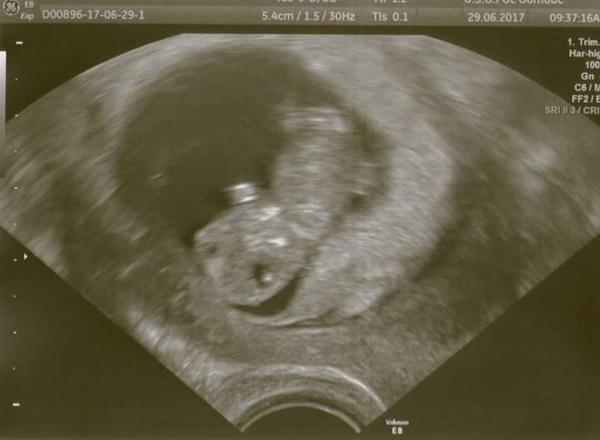

@llenka_li Moc gratuluji, UTZ krásný, je to úplně neuvěřitelné že tak brzy je to už takové miminko!